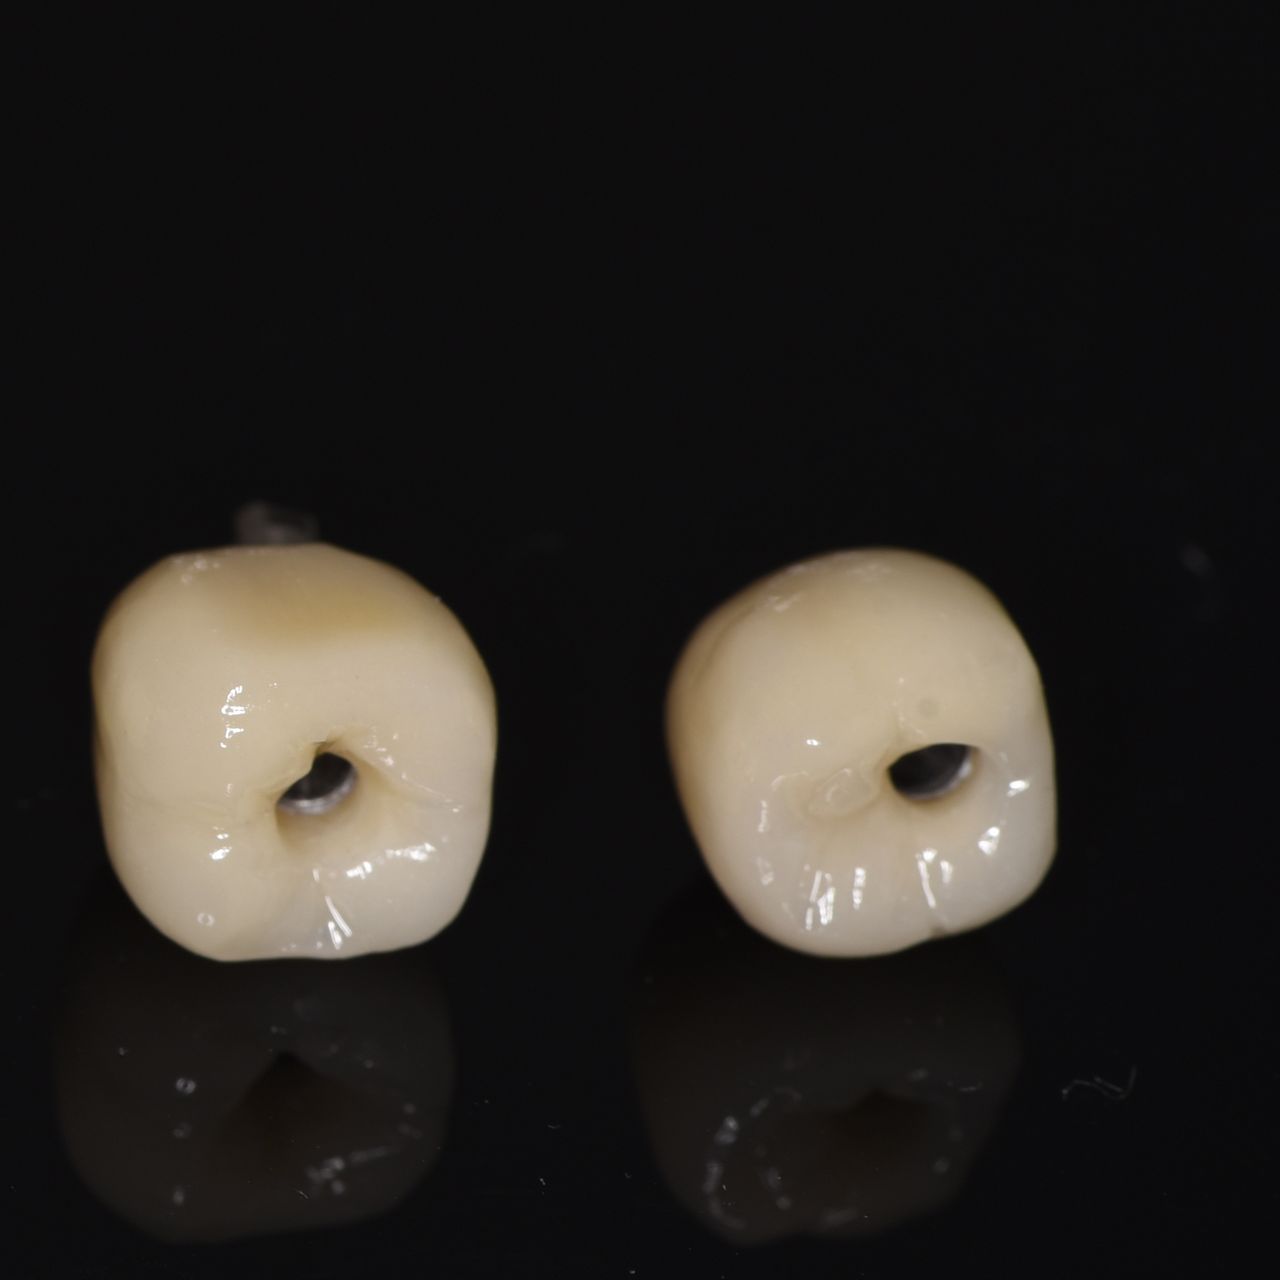

- protetyka (korony ceramiczne (cerkon, E-max), licówki, mosty, protezy ruchome, korony na teleskopach, inlay, onlay, overlay, endkorony);